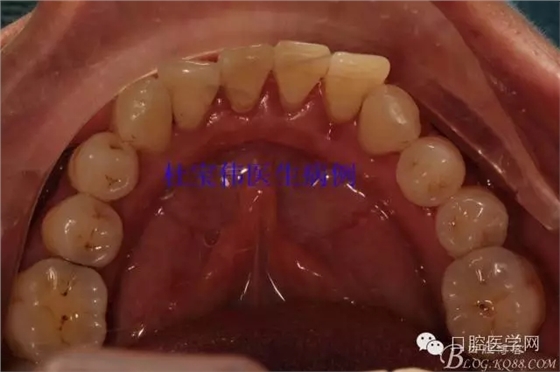

患者都是以刷牙出血為主訴。術(shù)前照片

術(shù)后照片

病例二術(shù)前照片